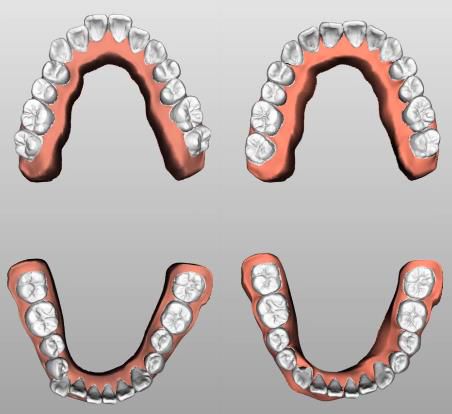

3D矯正軟體

• 以人工智慧為基礎的牙齒分離&分析技術

• 一般牙科醫生也能簡單樹立矯正計劃

• 可與其他設備互換牙齒模型CAD

Auto tooth separation   Auto tooth axis   Auto simulator for tooh alignment

Before After